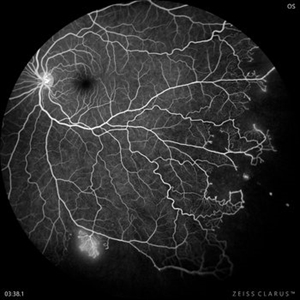

Proliferative Sickle Cell Retinopathy (Stage3) (10 files)

Proliferative Sickle Cell Retinopathy (Stage3) (10 files)

Sickle Cell Retinopathy (11 files)

Sickle Cell Retinopathy (11 files)

Sickle Cell Retinopathy SC (6 files)

Sickle Cell Retinopathy SC (6 files)